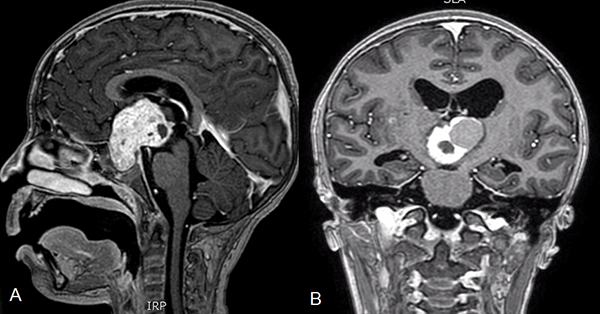

El tratamiento de craneofaringiomas mediante Ommaya ha pasado por diferentes estadios. Las primeras series trataban el quiste con Bleomicina,11,34 luego se intentó el tratamiento con Inteferón donde el equipo del SickChildren de Toronto presentó resultados muy alentadores,34 y por último la aspiración del quiste sin introducir ninguna sustancia.5 Drenar el quiste mediante el sistema de Ommaya es útil ya que permite que se reduzca el tamaño de la lesión y disminuye el contacto con las estructuras circundantes. Se encuentra descripto que luego de múltiples drenajes del quiste, la exéresis de la lesión es menos dificultosa debido a que presenta menos adherencias al hipotálamo, a la carótida interna o al quiasma.33 Otra ventaja del drenaje del quiste es que permite desbloquear los forámenes de Monro y mejorar la hidrocefalia obstructiva.3 Si bien nuestra serie de pacientes con Ommaya es muy reducida para sacar conclusiones definitivas, no encontramos un empeoramiento de las evaluaciones clínicas de los pacientes en el postoperatorio. Sin embargo, sólo 2 pacientes se mantuvieron estables luego del tratamiento, en los otros 5 casos se requirió de un tratamiento alternativo. Esto no debería considerarse como un mal resultado ya que la finalidad de la colocación del Ommaya no es curar la enfermedad sino retrasar los síntomas para permitirles a los pacientes una correcta maduración del eje (figura 3).

Figura 3. A. Resonancia cerebro corte sagital donde se observa tumor a predominio quístico en la región selar supraselar compatible con craneofaringioma. B. Tomografía de cerebro corte sagital postoperatoria de colocación de catéter intraquístico. C. Radiografía cráneo perfil donde se observa catéter radiopaco con extremo en la región selar.